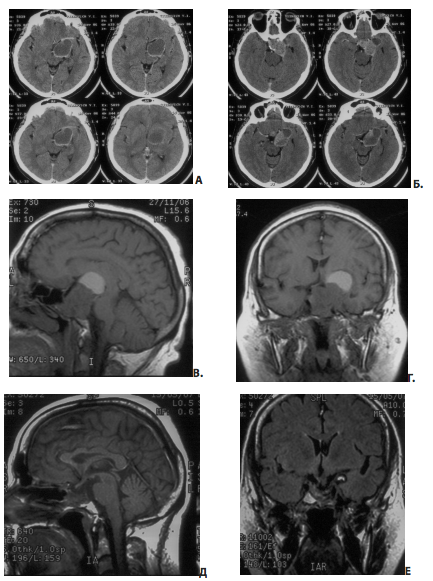

На рис. 11 представлен пример удаления гигантской эндо-супра-латероселлярной аденомы гипофиза — от задне-верхних отделов левого кавернозного синуса формировался крупный вырост опухоли с признаками старого кровоизлияния в него

Рис. 11. Пример удаления гигантской эндо-супра-латероселлярной аденомы: А, Б — КТ до операции; В, Г — МРТ до операции, Д, Е — МРТ через несколько месяцев после операции

Первым этапом была удалена эндо-супраселлярная часть опухоли под контролем 0 и 30-градусных эндоскопов. Затем под контролем 45º и 70º эндоскопов опухоль удалена из полости левого кавернозного синуса, в задних отделах синуса обнаружен вторичный узел опухоли, из его полости выделилось некоторое количество темно-бурой жидкости, после чего со стенок вторичного узла удалено небольшое количество опухоли (рис. 11, 12). При контрольной МРТ через несколько месяцев после операции явные остатки опухоли, в том числе и в полости кавернозного синуса, не определяются. Стрелкой указана складка капсулы удаленного вторичного узла.На рис. 13 представлен пример удаления большой эндо-супра-латероселлярной аденомы гипофиза. Однако, по данным контрольной КТ в первые сутки после операции, можно лишь сказать, что нами была удалена большая часть опухоли, но судить о том, есть ли остатки аденомы и какого они размера, достаточно сложно.

В данном случае радикальность проведенной операции была нами оценена как «субтотальная» (хирурги, осматривая полость кавернозного синуса во время операции, не видели явные остатки опухоли), однако вполне вероятно, что после получения результатов контрольного МРТ-исследования нам придется изменить наше суждение (в ту или другую сторону).

На рис. 14 представлен другой пример частичного удаления большой эндо-супра-латероселлярной аденомы гипофиза. По данным контрольной КТ на вторые сутки после операции, можно лишь сказать, что хирург удалял опухоль из синуса, однако очевидно, что удалена была не вся аденома, что также подтверждается субъективным мнением хирурга, отраженным в протоколе операции — плотные фрагменты аденомы, фиксированные к капсуле и стенкам сонной артерии, не удалялись.

Рис. 13. Пример субтотального (?) удаления большой эндо-супра-латероселлярной аденомы гипофиза: А, Б, В — МРТ до операции; Г, Д — КТ в первые сутки после операции

Рис. 14. Пример частичного (?) удаления большой эндо-супра-латероселлярной аденомы гипофиза: А — МРТ до операции; Б — КТ на вторые сутки после операции — в полости вторичного узла кровь, гемостатические материалы, остатки опухоли; оценить радикальность проведенной операции по данным КТ сложно

По данным контрольной КТ, произведенной не сразу после операции, достаточно сложно судить о радикальности проведенной операции — в образовавшейся полости скапливается кровь, кровью пропитываются гемостатические материалы, имбибируются остатки опухоли (рис. 14, Б).